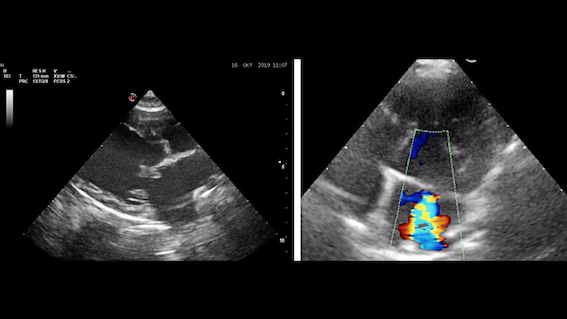

Die Mitralklappenendokardiose ist die häufigste erworbene Herzerkrankung beim Hund. Über 75 % der Hunde im Alter von über 13 Jahren leiden an einer mehr oder weniger ausgeprägten Form dieser Erkrankung. Es handelt sich bei der Mitralklappenendokardiose um eine Klappenerkrankung. Dabei kommt es dazu, dass sich die Herzklappen zwischen linker Vorkammer und linker Hauptkammer verdicken. Diese können infolge nicht mehr richtig schließen. Die Klappe wird undicht. Das Herz kann sich im Verlauf der Erkrankung vergrößern und es kann unter Umständen zu Symptomen wie Husten, Atemnot oder Ohnmachtsanfällen kommen. Die Erkrankung verläuft fortschreitend, allerdings ist die Geschwindigkeit des Fortschreitens sowie der Ausgang der Erkrankung individuell sehr unterschiedlich, sodass nicht jeder Hund mit einer Mitralendokardiose Symptome entwickelt oder gar daran stirbt (s. auch „Was passiert im Verlauf der Erkrankung – Schweregrade Stadien der Mitralendokardiose).

Hunde in einem frühen bis mittelgradigen Stadium zeigen keine Symptome. Mittels verschiedener Regelmechanismen kann der Körper die Erkrankung zumeist über einen langen Zeitraum kompensieren. Ab einem bestimmten Zeitpunkt schafft der Körper dies jedoch nicht mehr und es kommt zur Dekompensation. Ab dem Zeitpunkt der Dekompensation werden klinische Symptome für den Besitzer offensichtlich. Zu den häufigsten Symptomen zählen: Husten, schnelle Atmung oder Atemnot

Mitralklappendokardiose wird mittels Ultraschall bei einem Kardiologen untersucht |